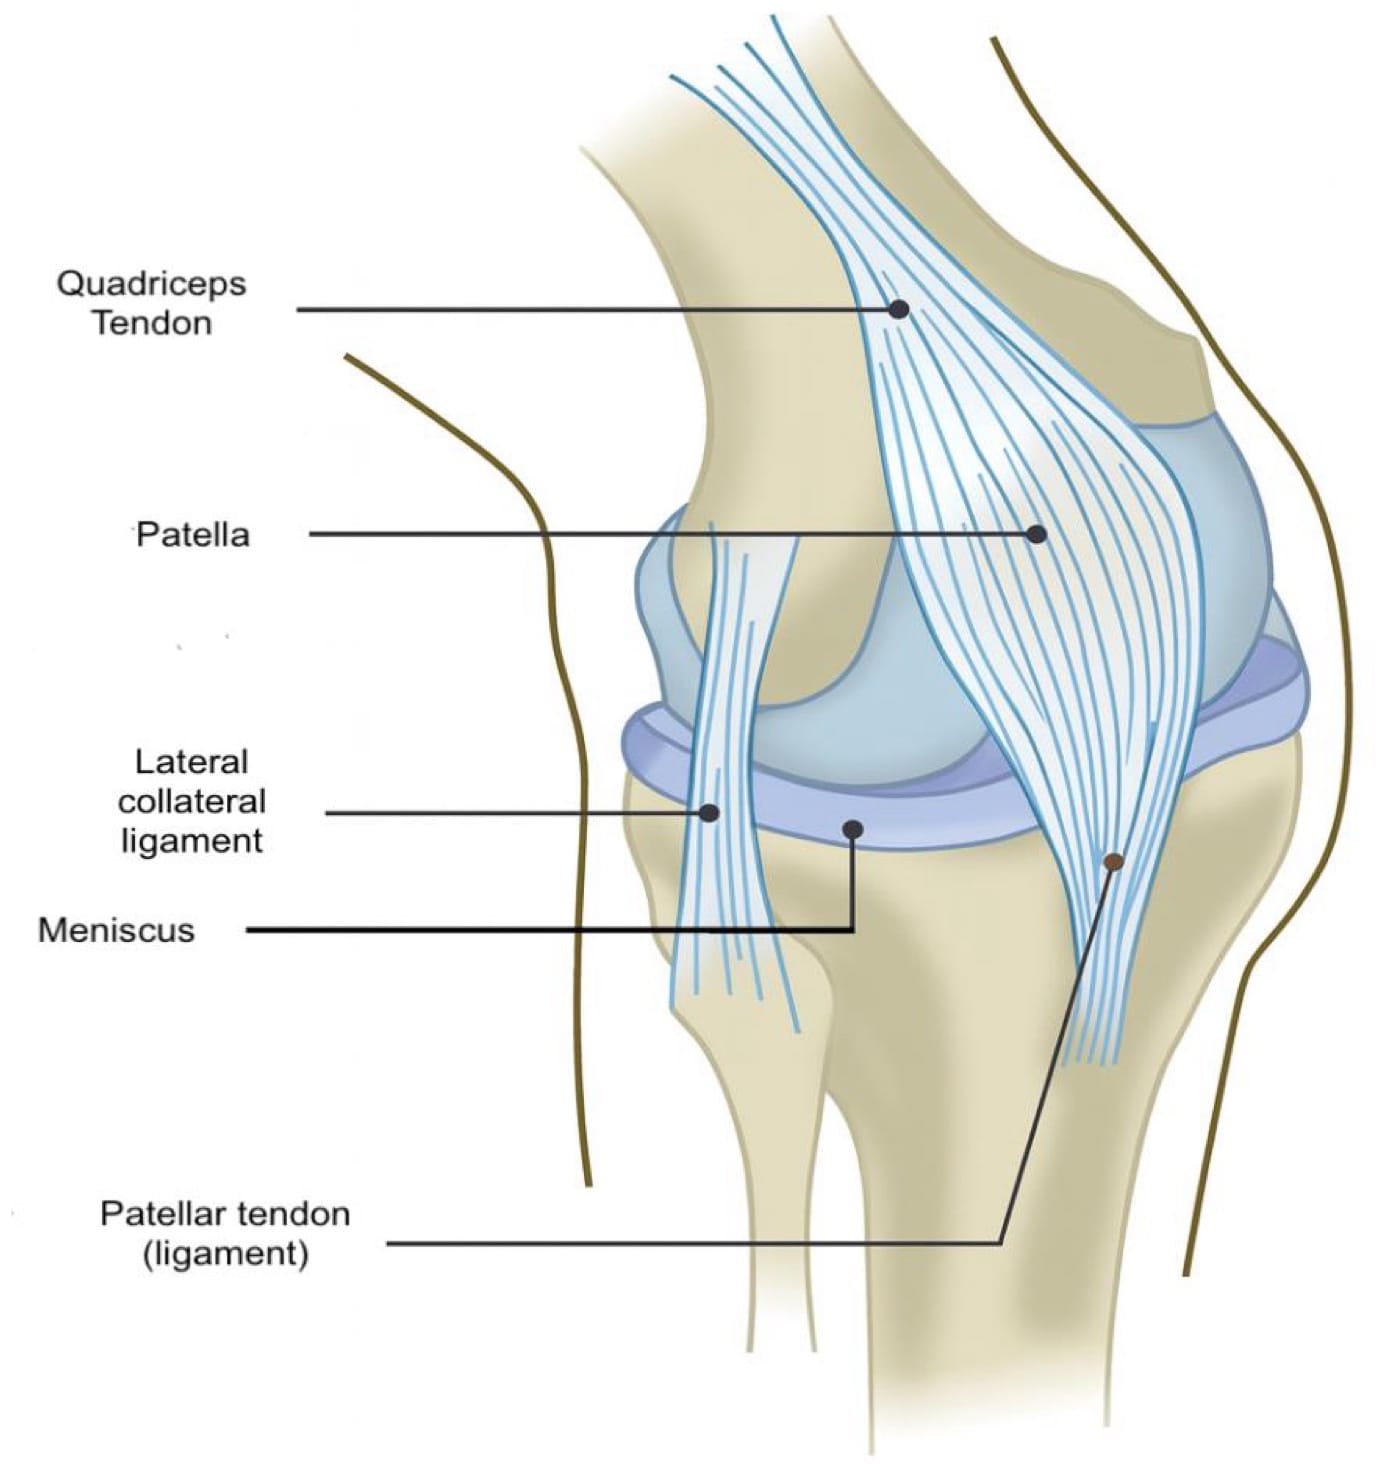

We recommend a high-frequency linear transducer (12–18 MHz). Providers can switch to a lower frequency transducer for larger body habitus or deeper structures. For anterior/medial and lateral visualization, the patient should be supine with the knee slightly flexed at 20–30° on a towel roll (Figures 1A and B, 2, and 3). For posterior, the prone position is preferred (Figure 4).

Begin by placing the transducer in short axis over the quadriceps muscle (“home base”). Rotate into long axis and scan distally over the tendon to the superior pole of the patella (Figures 1A and B).

Just beneath the tendon lies the quadriceps fat pad, followed by the suprapatellar recess, which appears as an anechoic stripe when effusion is present (Figures 5C, D).

The prefemoral fat pad above the femur provides another landmark. Continue to the patella itself in both long and short axis, assessing for cortical irregularities, fracture, or bipartite variants. Between the skin and bone lies the prepatellar bursa, a potential space for fluid that is best evaluated with minimal transducer pressure, and plenty of gel (Figure 5B).

From the patella, trace the patellar tendon distally in long axis toward its tibial insertion, then rescan in short axis for completeness. At the tibial tubercle, evaluate the tendon attachment as well as the adjacent bursae.

The superficial infrapatellar bursa lies superficial to the distal aspect of the patellar tendon, while the deep infrapatellar bursa sits slightly proximally and beneath it against the tibia. Of note, the deep infrapatellar bursa typically contains physiologic fluid, whereas the superficial infrapatellar bursa does not usually contain fluid under normal conditions. Deep to the tendon throughout its course is Hoffa’s fat pad, a bright or hyperechoic structure that should be assessed for contour or echogenicity changes.

Key Structures: Quadriceps tendon, patella, patellar tendon, suprapatellar recess (Figures 5A-D).